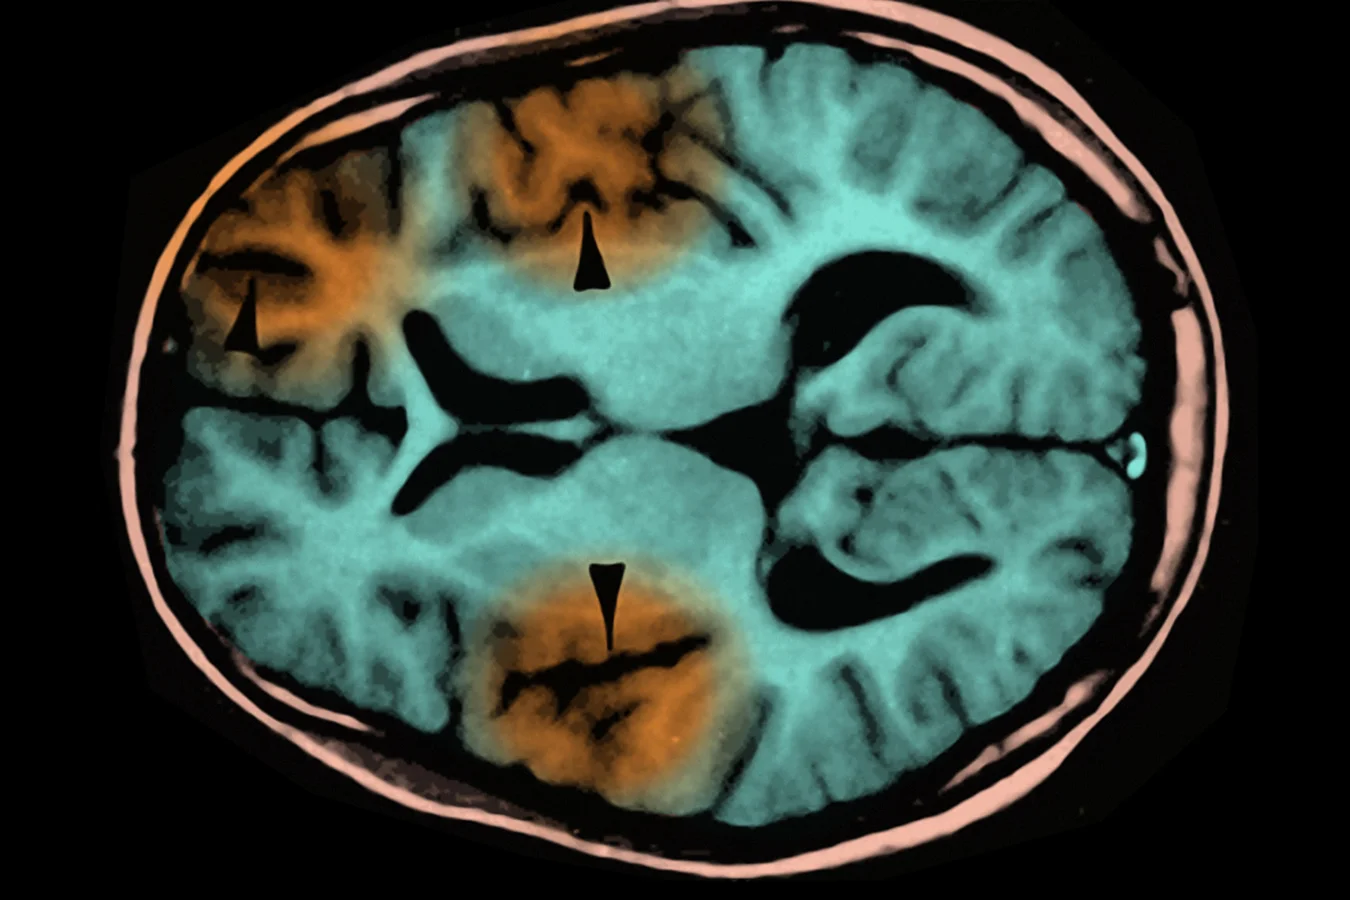

در لسآنجلس، یک کودک مدرسهای جان خود را به دلیل پیامد دیررس و مرگبار سرخک از دست داد. این کودک در نوزادی به ویروس سرخک مبتلا شده بود؛ زمانی که هنوز برای دریافت نخستین دوز واکسن کوچک بود. سالها بعد، ویروسی که در بدن او پنهان مانده بود، در مغز بیدار شد و به بیماریای به نام «انسفالیت اسکلروزان تحتحاد» (SSPE) انجامید؛ اختلالی که همواره کشنده است و هیچ درمانی برای آن وجود ندارد.

به گزارش ساینتفیک آمریکن، این پرونده بار دیگر یادآور میشود که سرخک بیماری سادهای با تب و لکههای پوستی نیست. ویروس میتواند در بدن پنهان شود، به مغز مهاجرت کند و سالها بعد با تخریب پیشرونده سلولهای عصبی جان بیمار را بگیرد. پزشکان توضیح میدهند که در SSPE، ویروس دچار جهشهایی میشود که آن را از دید سیستم ایمنی پنهان میکند. نتیجه آن است که دفاع طبیعی بدن خاموش میشود و ویروس بدون مانع بافت مغز را از بین میبرد. از آغاز علائم، بیمار معمولاً ظرف یک تا سه سال جان میبازد. خطر این عارضه در کودکانی که در نوزادی مبتلا میشوند، بهمراتب بیشتر است و ممکن است به یک مورد در هر ۶۰۰ ابتلا برسد.